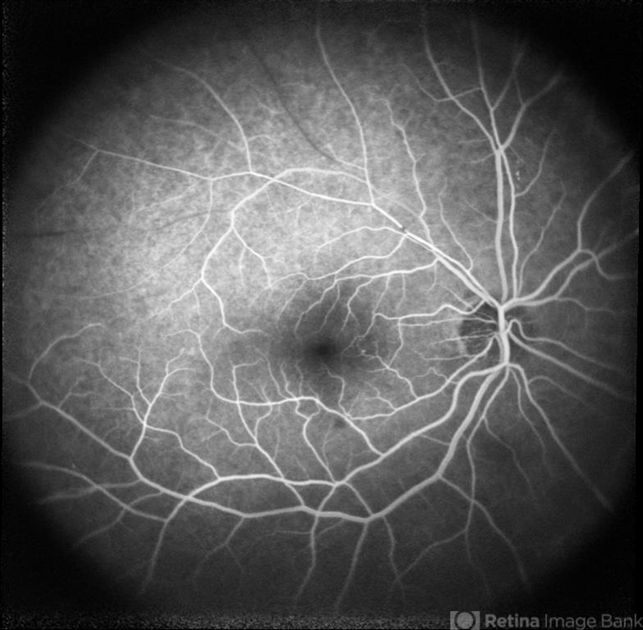

- branch retinal vein occlusion (BRVO), nonproliferative diabetic retinopathy

- Fluorescein angiography of a 77-year-old woman with ischemic occlusion of the superior temporal branch of the central retinal vein with non-proliferative diabetic retinopathy.